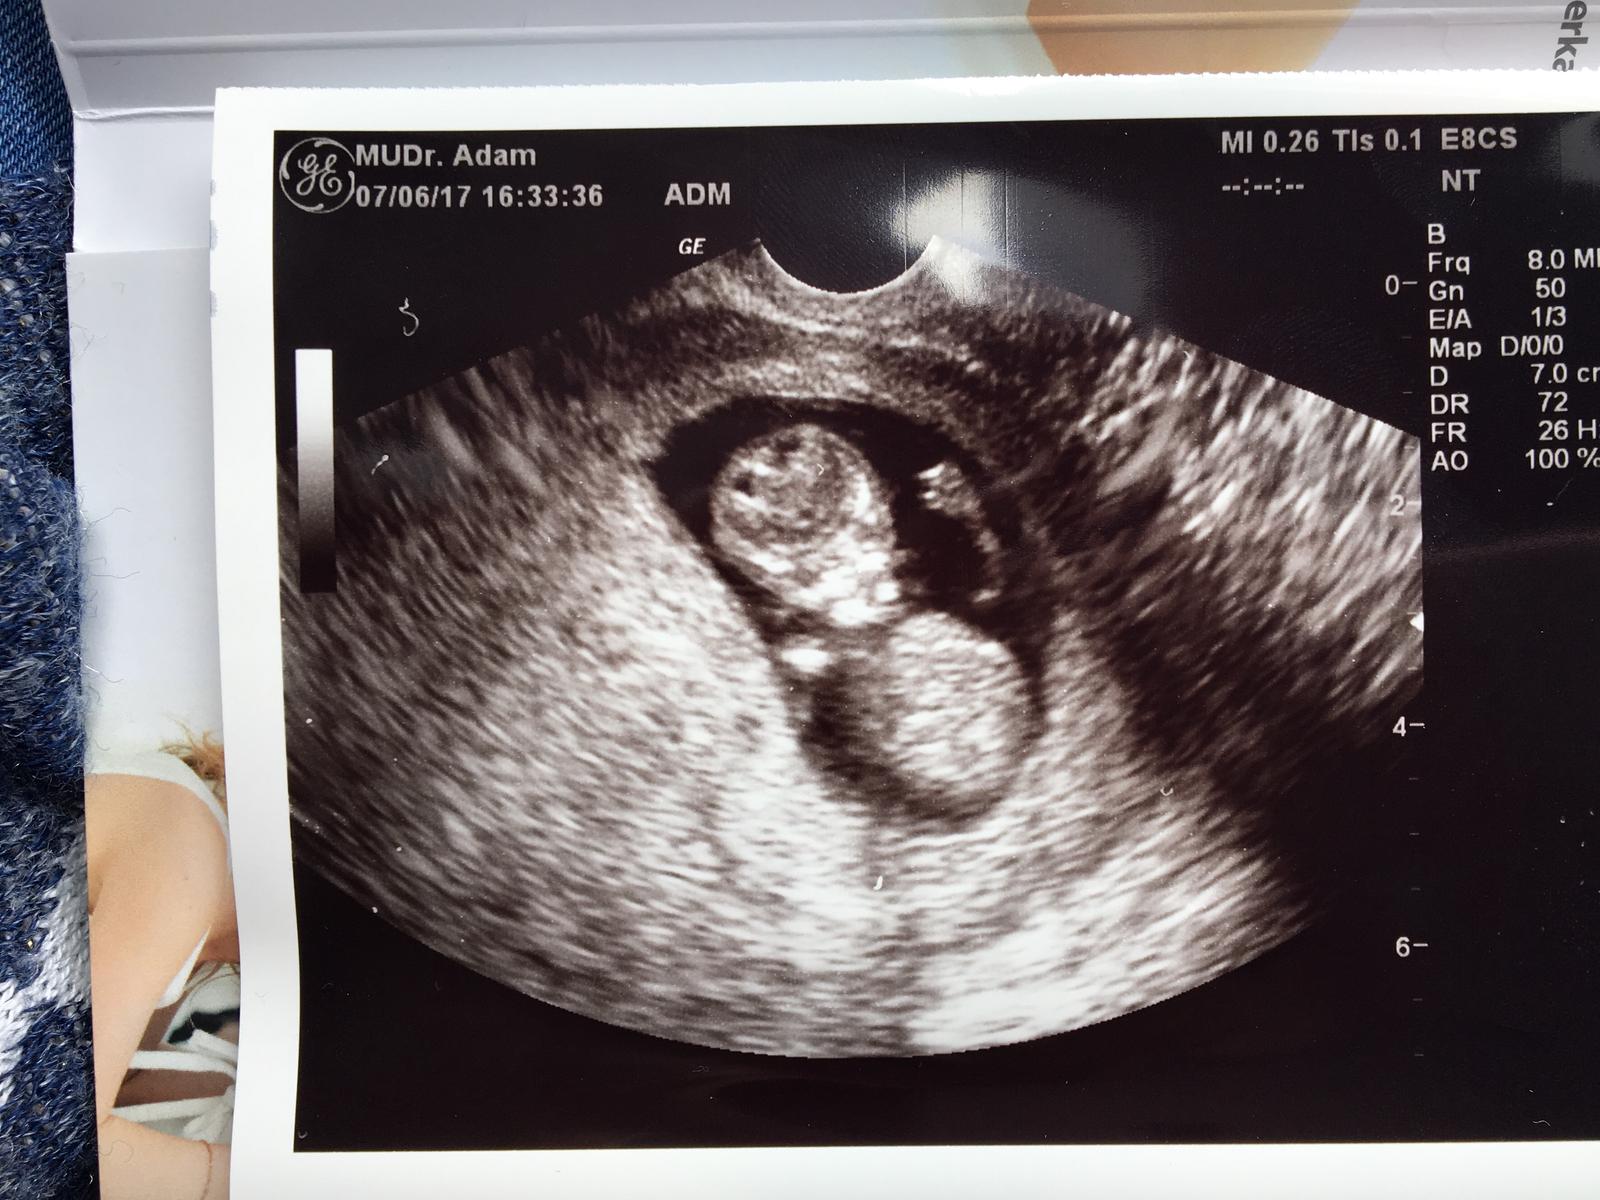

Baby,tak vsetko je v poriadku, vydledky z krvi su super 🙂 boooze,skoro som sa rozrevala ked som uvidela ako sa krasne hybalo...ruckami,nozickami..dokonca aj skackalo... chvilku si tvaricku suchalo ... nadherne to bolo ❤️❤️❤️❤️ TP tak ako som si vyratala: 30.12. a podla velkosti sme 10tt 6 dni,cize je asi o 3 dni vacsie ako podla MS... veeeelmi som stastna, dakujem ,ze ste na mna mysleli 😘😍